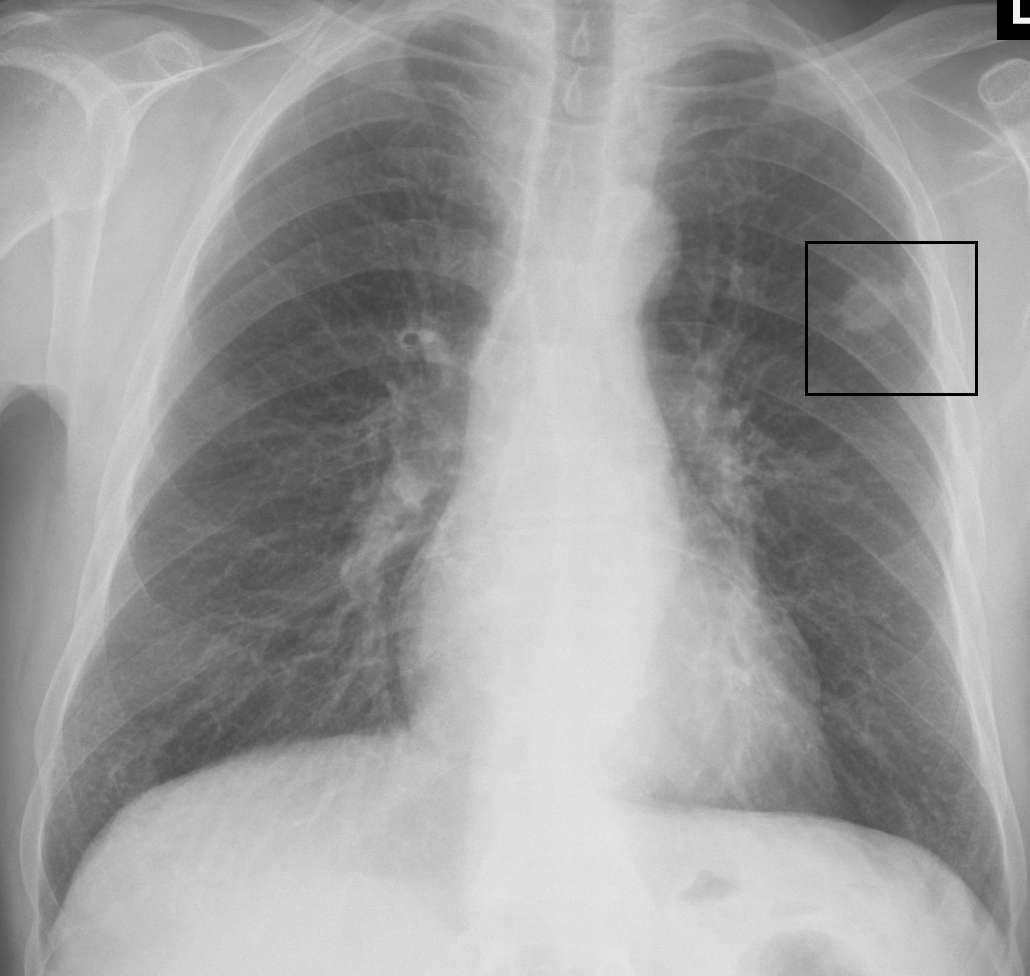

말초 기관지 암종을 나타내는 흉부 방사선 사진

3. 5. 의료 분야

몇몇 비파괴 검사 방법은 방사선 검사, 초음파 검사, 육안 검사 등 임상 절차와 관련이 있다.[56][57] 이러한 비파괴 검사 방법의 기술적 개선 또는 업그레이드는 디지털 방사선 검사(DR), 위상 배열 초음파 검사(PAUT), 그리고 내시경 (보어스코프 또는 보조 육안 검사)을 포함하여 의료 장비 발전에서 비롯되었다.